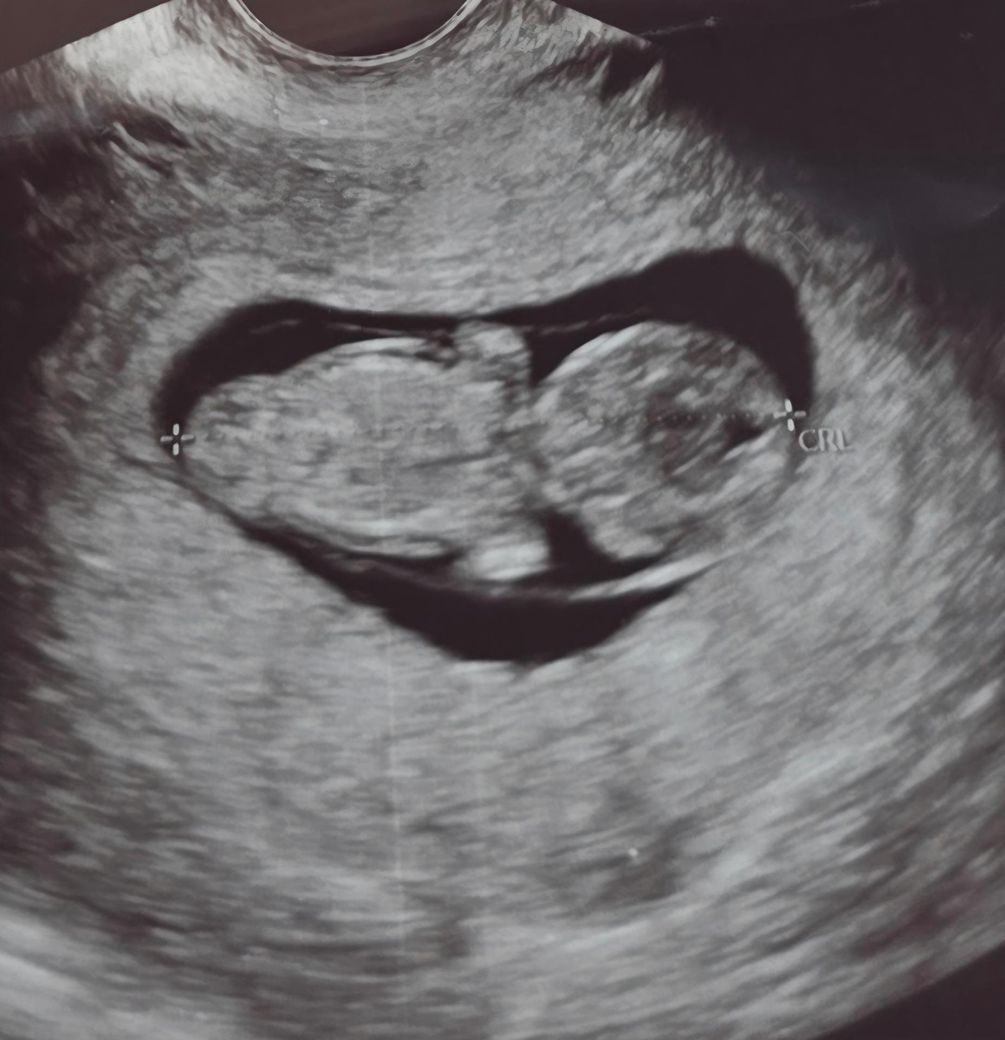

• 1번 째 사진

올려주신 영상에서는 태아 주변으로 피하 부종처럼 보일 수 있는 저에코 영역이 약간 두꺼워 보이기는 합니다. 다만 단일 이미지로 확정적으로 “태아수종이다”라고 진단할 수 있는 수준은 아닙니다. 실제 진단은 다음 기준이 필요합니다. 흉수, 복수, 심낭삼출 중 최소 두 가지 이상이 동반되어야 태아수종으로 정의됩니다. 현재 사진만으로는 그 정도까지는 명확히 확인되지 않습니다.